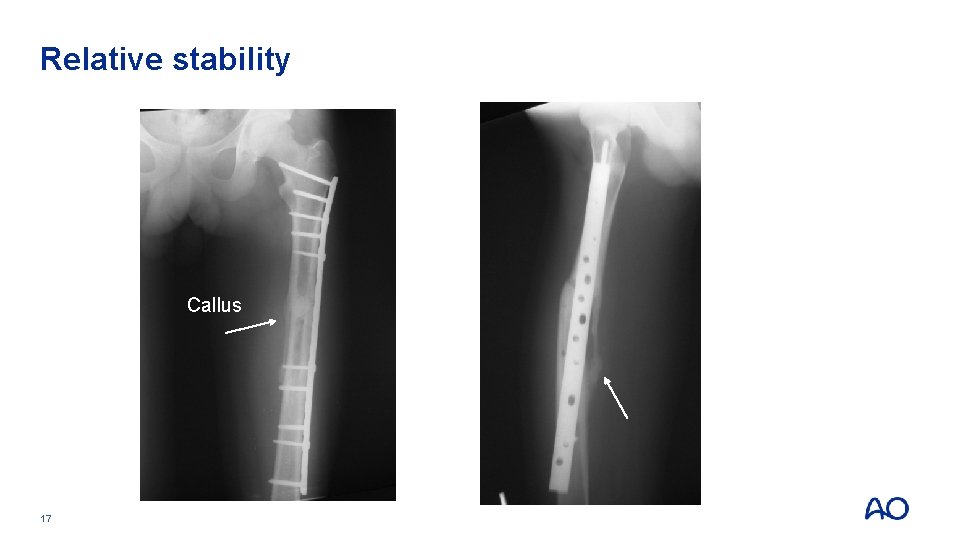

Relative stability Callus 16

Relative stability Callus 17